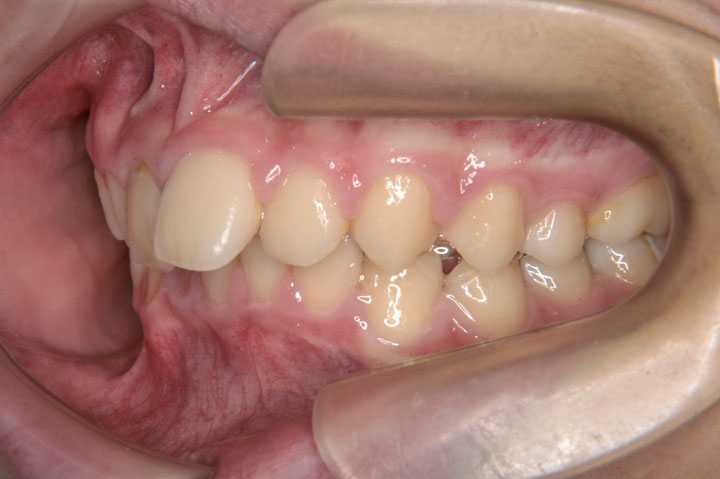

前歯部不正(交叉咬合など)

叢生(乱ぐい歯)

口唇口蓋裂

欠損歯

先天性口唇口蓋裂患児で小学校2年生の男子です。前歯部交叉咬合を認め、下顎前歯の歯肉が退縮しダメージの大きい状態でした。そのためリンガルアーチによる前歯部被蓋改善より開始し、その後拡大処置に行っております。上顎右側側切歯が欠損でしたが、ご父兄と相談の結果、反体側の抜歯による無理な正中線の補正はおこなわずエッジワイズ治療に移行しております。またダメージの大きかった下顎前歯の歯肉は回復することができ、良い治療結果であったと思っております。